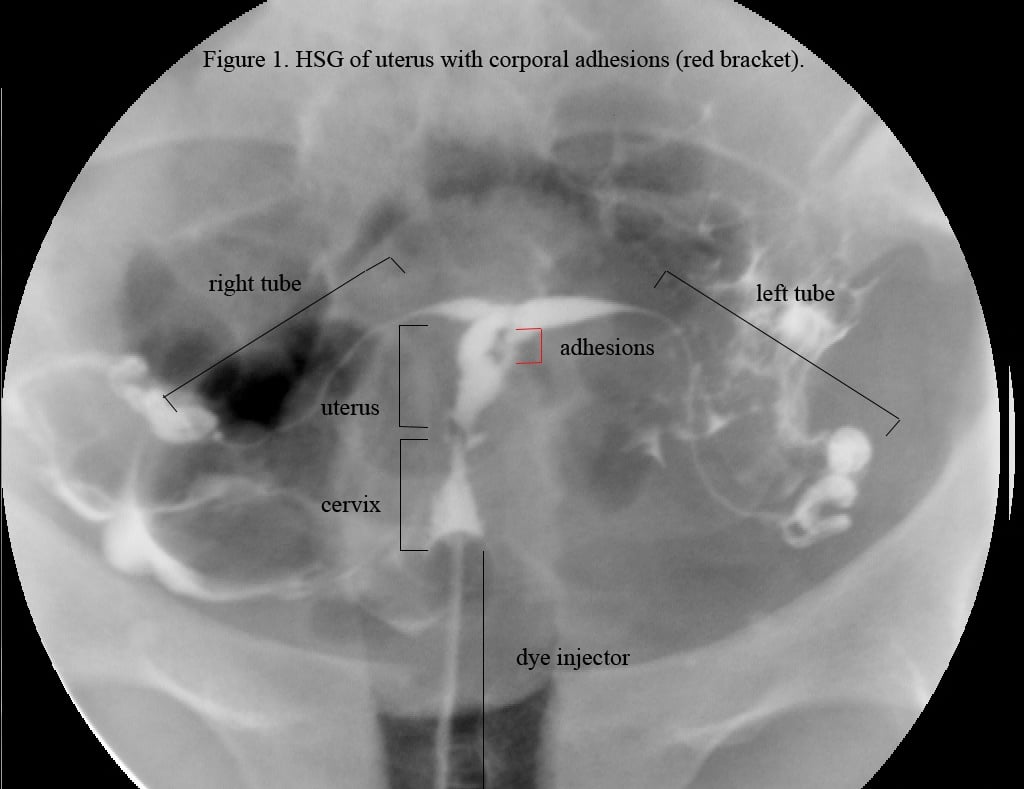

If there are no blockages, the contrast material will fill the uterus, flow easily through the fallopian tubes, and dissipate into the abdominal cavity around each ovary. If there are any blockages or abnormalities, the flow of the contrast material will be interrupted and visible on the X-ray photos.[2] X-ray images may be taken at various angles to get a clear picture of the path of the contrast material and any anomalies, adhesions, or obstructions in the uterus or fallopian tubes.